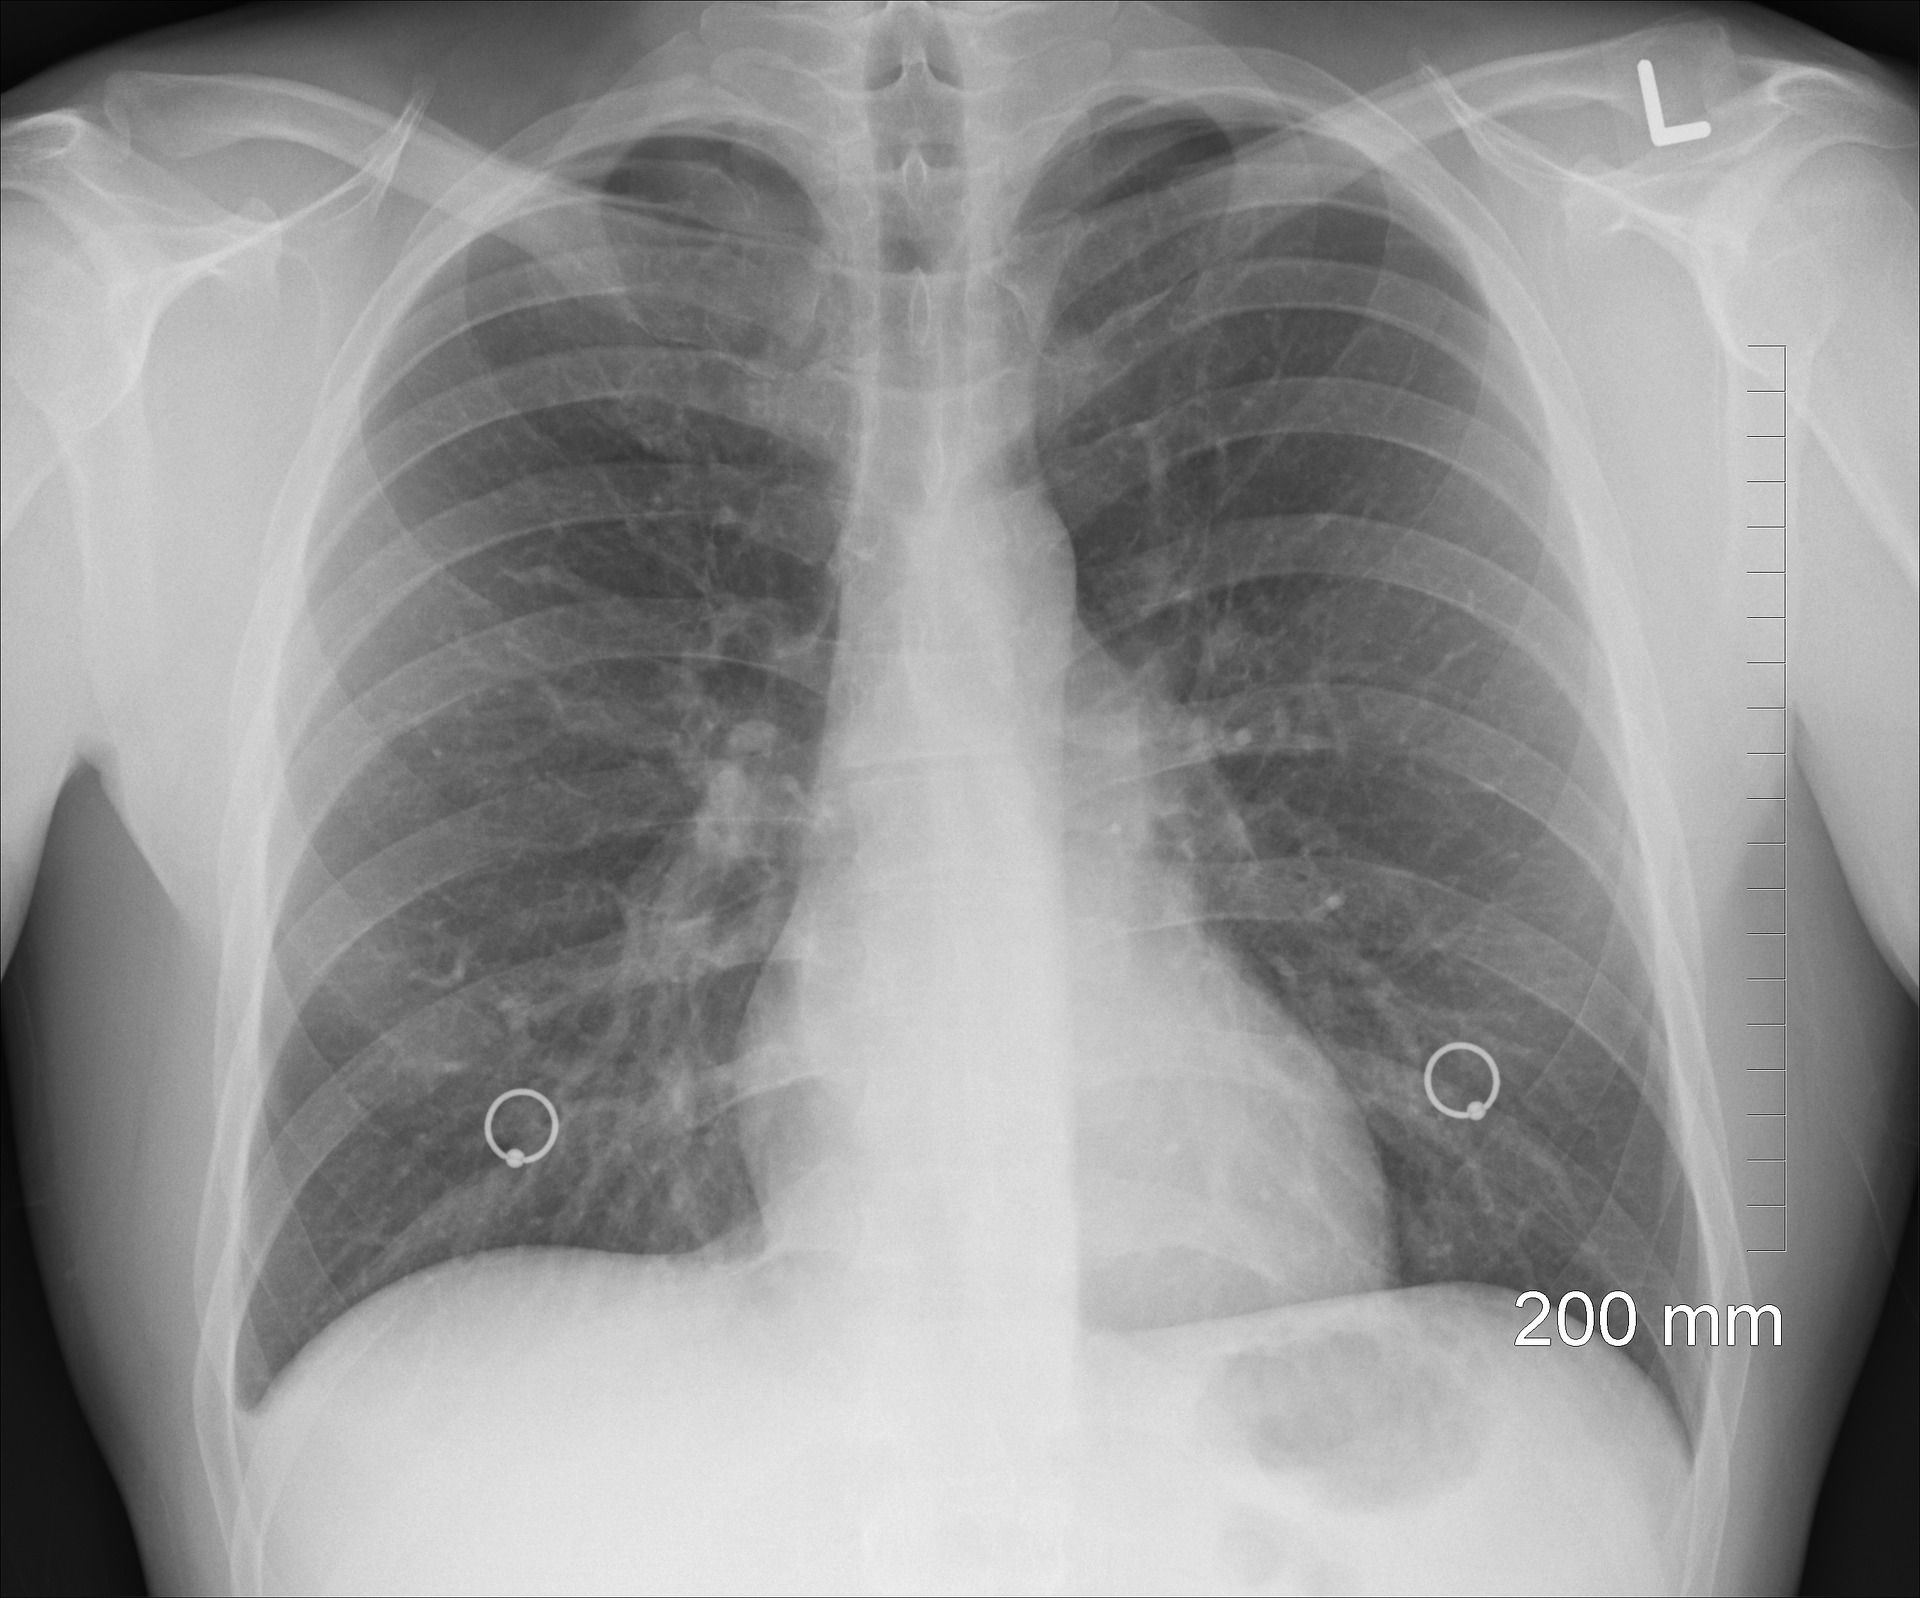

Om zeker te weten of je een longontsteking hebt, kan het zijn dat er een röntgenfoto wordt gemaakt. Op de foto is duidelijk te zien of en waar er een ontsteking is en hoe groot deze is. Als blijkt dat het om een niet-bacteriële longontsteking gaat, wordt meestal ook het bloed onderzocht op andere oorzaken.